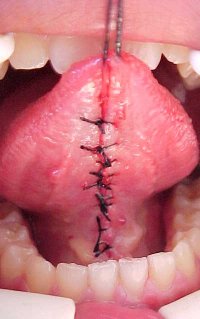

Tratamento cirúrgico da "Língua Presa". Frenectomia ou Frenulotomia Lingual

| Esta técnica cirúrgica destina-se à liberação dos movimentos funcionais da língua . Neste caso a inserção mais anterior se mostra aderida à gengiva:

| Cirurgia realizada pelo Dr. Amilcar Fernandes Neto. |